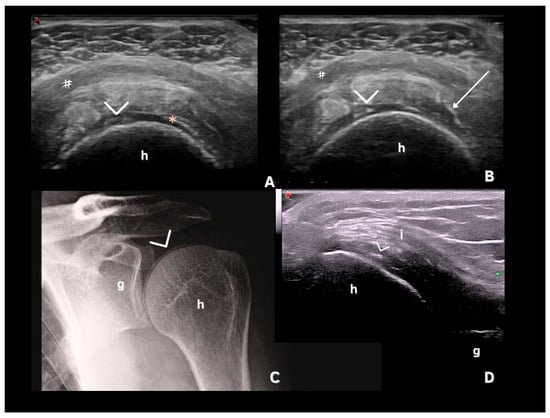

- Filippucci, E.; Delle Sedie, A.; Riente, L.; Di Geso, L.; Carli, L.; Ceccarelli, F.; Sakellariou, G.; Iagnocco, A.; Grassi, W. Ultrasound imaging for the rheumatologist. XLVII. Ultrasound of the shoulder in patients with gout and calcium pyrophosphate deposition disease. Clin. Exp. Rheumatol. 2013, 31, 659–664. [Google Scholar]

- Di Matteo, A.; Filippucci, E.; Cipolletta, E.; Musca, A.; Carotti, M.; Mashadi Mirza, R.; Jesus, D.; Martire, V.; Pierucci, D.; Di Carlo, M. Hip Involvement in Patients With Calcium Pyrophosphate Deposition Disease: Potential and Limits of Musculoskeletal Ultrasound. Arthritis Care Res. (Hoboken) 2019, 71, 1671–1677. [Google Scholar] [CrossRef]

| Fibrocartilage | Shape: Deposits of variable shape. Echogenicity: Hyperechoic (similar to the bone cortex echogenicity). Localization: Within the fibrocartilage structure. Dynamic scanning: Remain fixed and move together with the fibrocartilage during dynamic assessment. Examples: Menisci, TFC, hip labrum, and acromioclavicular joint. |

| Hyaline cartilage | Shape: Deposits of variable shape. Echogenicity: Hyperechoic, without posterior shadowing. Localization: Localized within the hyaline cartilage. Dynamic scanning: The deposits remain fixed and move together with the hyaline cartilage. Examples: Knee and MCP joint. |

| Pseudo-double contour sign | Shape: Deposits of variable shape. Echogenicity: Hyperechoic, without posterior shadowing. Localization: Localized at the chondro-synovial interface or in the joint capsule and adjacent ligaments. Dynamic scanning: Moves in the opposite direction of cartilage and adjacent bone. Examples: Knee, proximal, and distal radio-ulnar joint. |